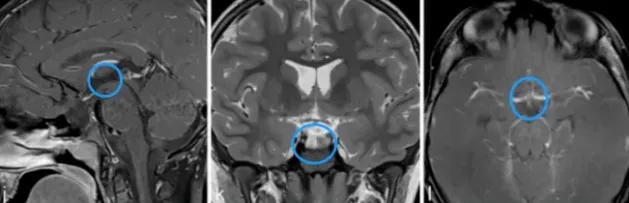

一张核磁共振影像揭示真相:低精力表象下的全垂体功能减退

一张核磁共振影像彻底改变了乐乐的生活。原来,“低精力”仅仅是一个表象,更深层的原因在于他生病了。在就诊前的一个月内,乐乐的变化不仅限于疲劳感,体重下降、身高增长停滞、抵抗力降低、头痛呕吐……这些症状接踵而至,共同指向了一个令乐乐妈妈感到陌生的疾病——全垂体功能减退。

然而,深入探究之下,乐乐之所以患上全垂体功能减退,根源在于他脑内的一个异常阴影,医生怀疑其为颅咽管瘤。这无异于晴天霹雳,当前若要根治乐乐的全垂体功能减退,势必要切除这个肿瘤。